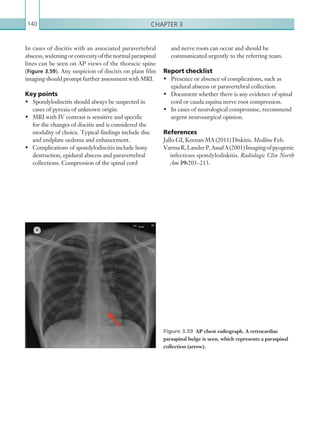

Standard 15. Angiographic facilities and

endovascular theatres in MTCs should be

safe environments for SIPs and should be

of theatre standard.